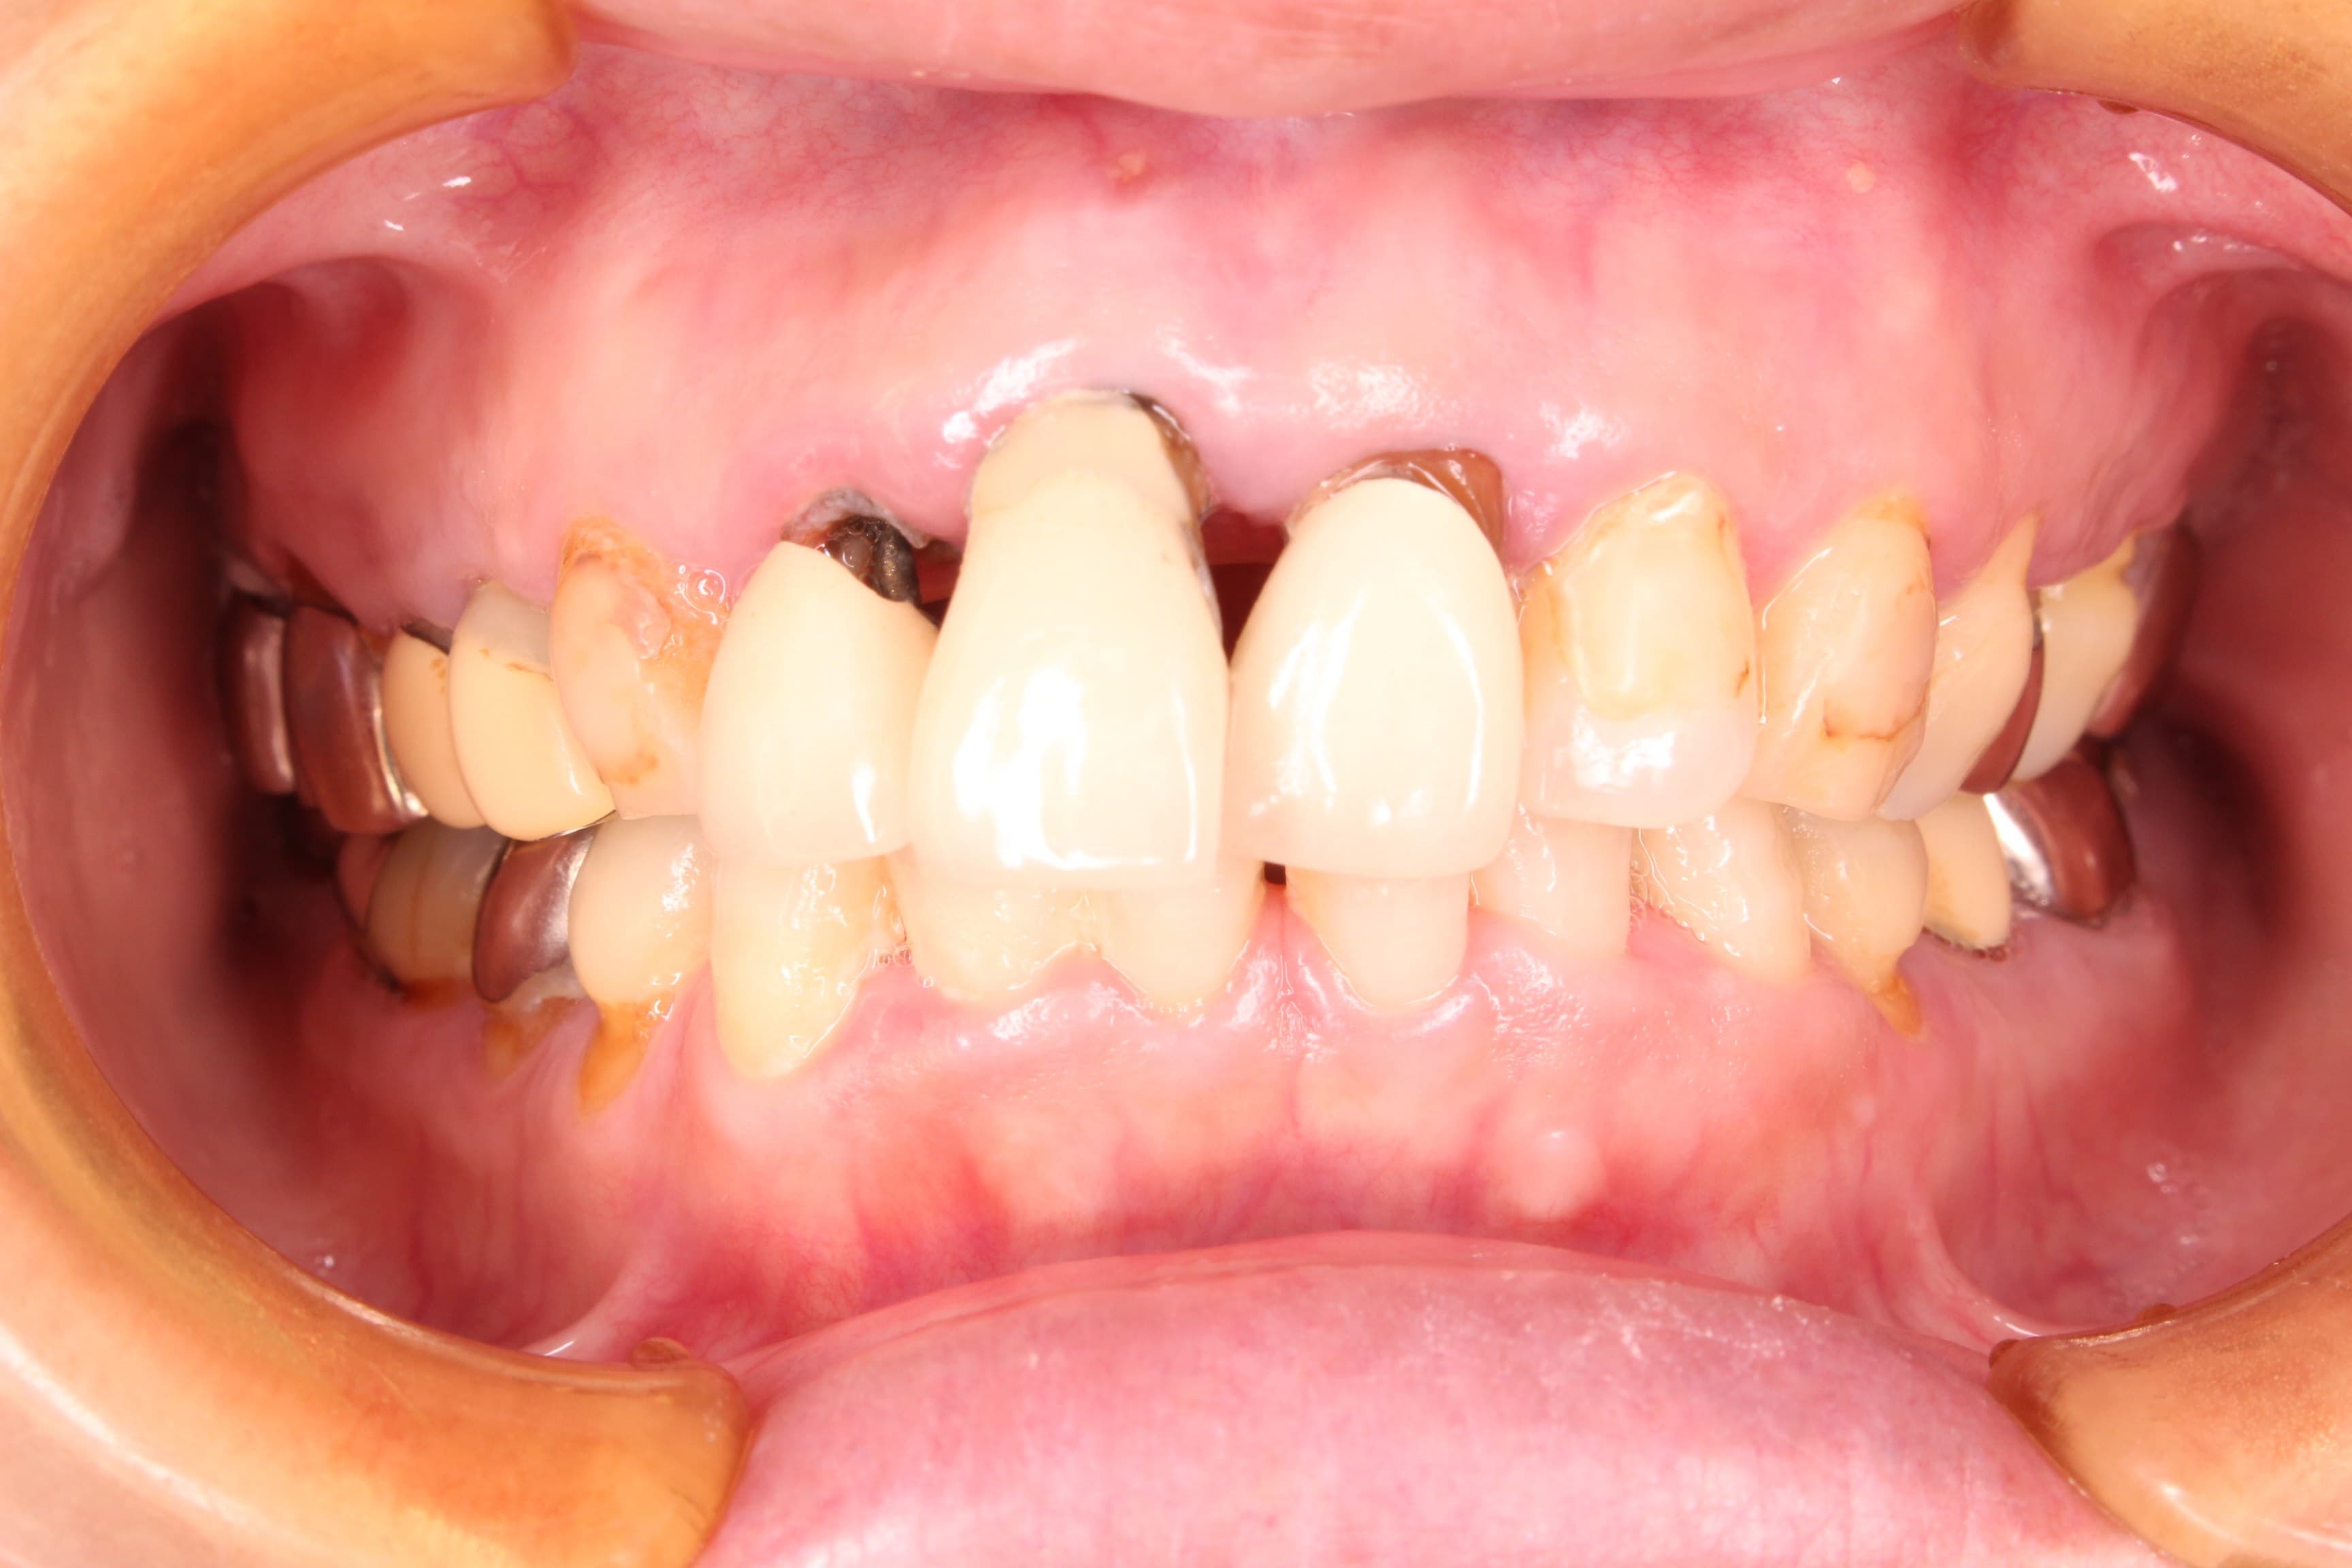

今回ご紹介する歯周専門治療のケースは、50代女性の方です。

虫歯の治療を希望されて来院されました。

口腔内の状態は、虫歯も大きく進行し、歯周病のコントロールもされておらず、出血やプラーク、歯石等の感染物質も大量に付着していた為、虫歯の治療ができる状態ではありませんでした。